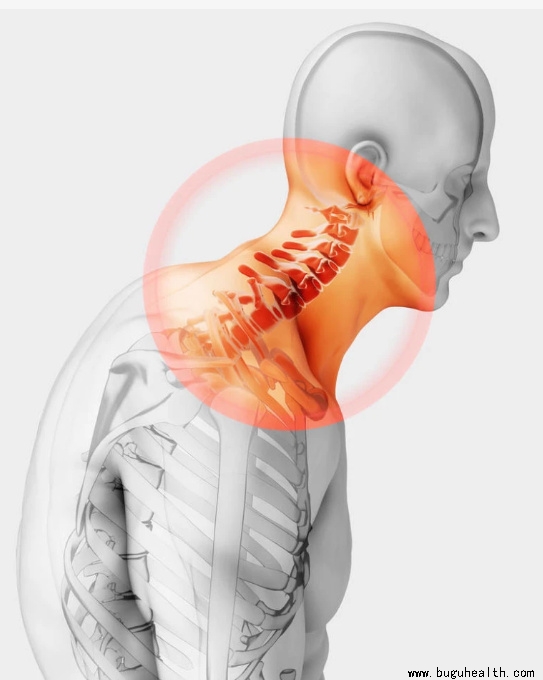

- 布骨医学科普:脖子咔咔响,当心「颈椎病」!护颈指南为您奉上 BuGuRMC布骨康复医疗中心 ,2023-03-14

- 在平时的工作与生活中,如果你长时间保持一个姿势会不会感觉颈部非常不舒服,此时你扭一扭脖子有时会发出“咔咔”的响声。此时你是不是会怀疑自己得了颈椎病?.....